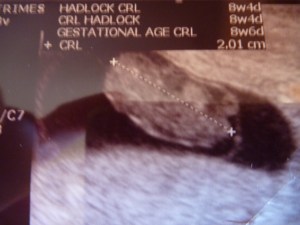

A few months later I became pregnant again and this time I knew. I had the same feeling of being nauseous every day and I was sick. Taking a test, it confirmed I was pregnant. I knew from very early on. I seemed to be growing my bump quite quickly so I wondered if I was further along then I previously thought because I am rubbish with writing down my cycle dates I was actually guessing at my last! When I got the dating scan at the hospital they saw 2 heartbeats and it was twins at 10 weeks and 2 days so I had been slightly off with my calculations but it explained why I was bigger. OMG we were on cloud nine! Twins! I just kept hugging myself and feeling a surge of happiness and excitement imagining my children. 2 in one go!

The hospital said they were monozygotic twins, identical twins from the same zygote. I looked at them on the screen moving around, these 2 small blobs that meant the world to me. We kept looking at the scan picture and smiling. We phoned all our friends and relatives and told them and showed our picture. The hospital scheduled us to come back the next week for another scan as twins were a little riskier and whilst feeling so happy, that set off alarm bells in my head. They said that whilst there is a 1 in 4 chance of each pregnancy failing, there is only a 1 in 4 chance of a monozygotic pregnancy surviving. But I quelled the little worm of doubt and kept looking at my scan photo and the 2 pairs of booties I had bought (the only things I had bought) and feeling that rush of happiness.